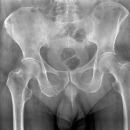

Becken / Hüfte

Fraktur Ramus pubis sup. und inf.